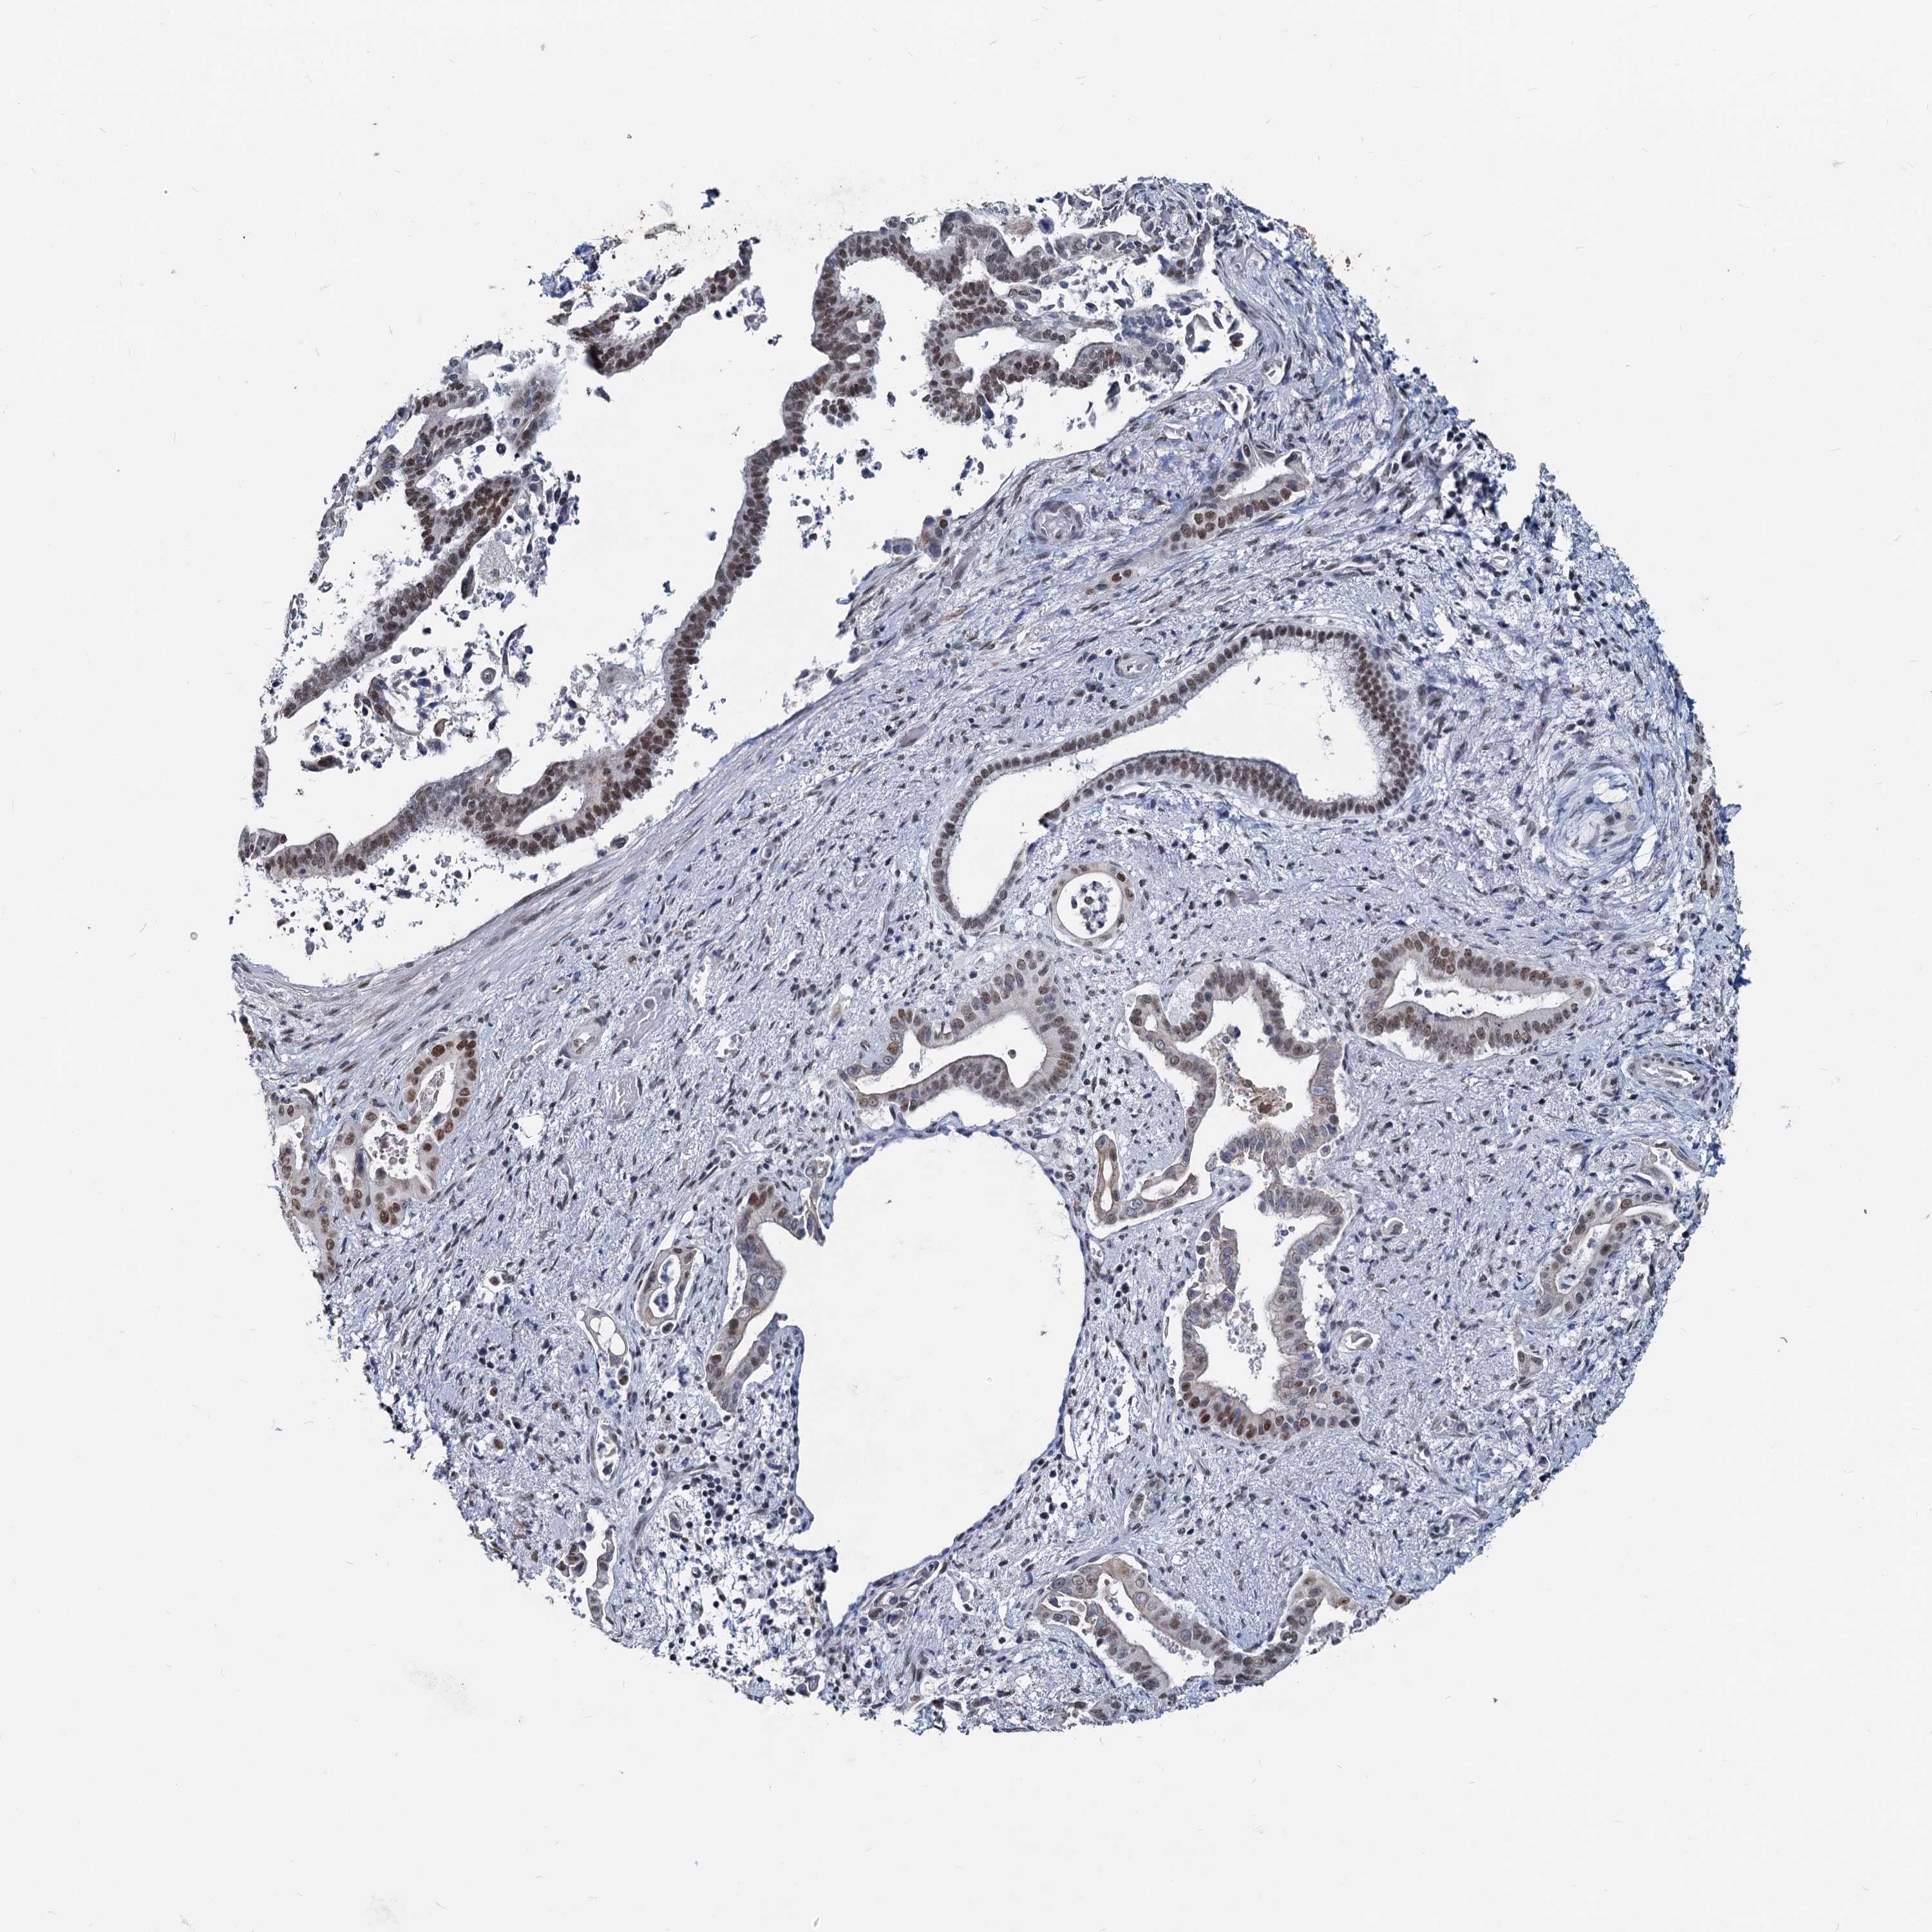

PANCREATIC CANCER - Protein expressioni

A mouse-over function shows sample information and annotation data. Click on an image to view it in a full screen mode. Samples can be filtered based on level of antibody staining by selecting one or several of the following categories: high, medium, low and not detected. The assay and annotation is described here.

Note that samples used for immunohistochemistry by the Human Protein Atlas do not correspond to samples in the TCGA dataset.

Antibody stainingi

Antibody staining in the annotated cell types in the current human tissue is reported as not detected, low, medium, or high, based on conventional immunohistochemistry profiling in selected tissues. This score is based on the combination of the staining intensity and fraction of stained cells.

Each image is clickable and will lead to virtual microscopy that enables deeper exploration of all samples and also displays staining intensity scores, fraction scores and subcellular localization as well as patient and tissue information for each sample.

Antibody HPA038002

Staining

High

Medium

Low

Not detected

Intensity

Strong

Moderate

Weak

Negative

Quantity

>75%

75%-25%

<25%

None

Location

Nuclear

Cytoplasmic/membranous

Cytoplasmic/membranous,nuclear

Adenocarcinoma, NOS